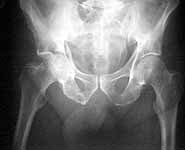

63 year old male, simple fall 4 days ago with an undisplaced Right Surgical neck of humerus fracture and this acetabular fracture. My assessment is that it is an anterior wall & column fracture with a blow out of the quadrilateral plate. the posterior column is intact. I see the immediate options as an attempted closed reduction and traction or an open reduction. I am right in saying this would need to be openly reduced through an ilioinguinal approach (which I have never seen or done). Or do I wait and do his Total Hip Replacement when his fracture has healed?